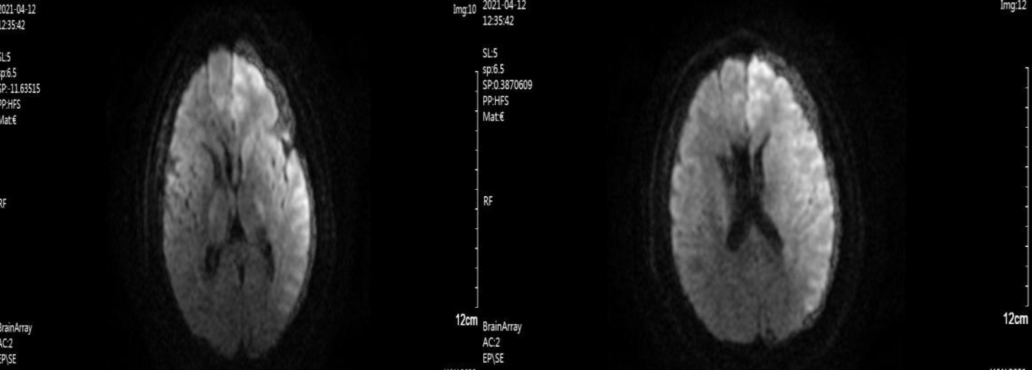

完善颅脑磁共振:

1.DWI示左侧额叶、颞叶及顶叶急性梗死灶。FLAIR示左侧大脑半球未见明显显影。FLAIR及DWI不匹配。

术前DWI

术前MRA